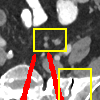

Effect of metal mask projection (SE0-Net vs SE-Net). From Table 1, we can observe the use of instead of improves the performance for at least 4.1 dB in PNSR and reduces MSE from 0.95219 to 0.00074 for all metal sizes. The groups with large metal implants benefit more than groups with small metal implants. As shown in Fig. 4, the artifacts in metal trace of SE0-Net are over-removed or under-removed, which introduces bright and dark bands in the reconstructed CT image. With the help of , SE-Net can suppress the artifacts even when the metallic implants are large and the surrogate data are more consistent with the correct data outside the metal trace.

Effect of sinogram padding (SE-Net vs SEp-Net). Sinogram padding mainly improves the performance in the group with the largest metal objects, with a PSNR gain of 0.15 dB and an MSE reduction of 0.00048. As shown in Fig. 4, the model with sinogram padding restores finer details of soft tissue between large metallic objects because more correct information is retained by periodic padding than zero-padding.

Effect of learning with (SEp-IE-Net vs Ours). When is jointly restored with the corrupted , the sinogram correction performance is affected with an increment of 0.00033 in MSE and of 0.7 dB in PSNR. More details of soft tissue around metal are retained and the image becomes sharper, as shown in Fig. 4.